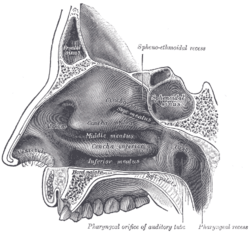

Medial wall of left orbit. Lateral wall of nasal cavity.

Lateral wall of nasal cavity. Sagittal section of nose mouth, pharynx, and larynx.